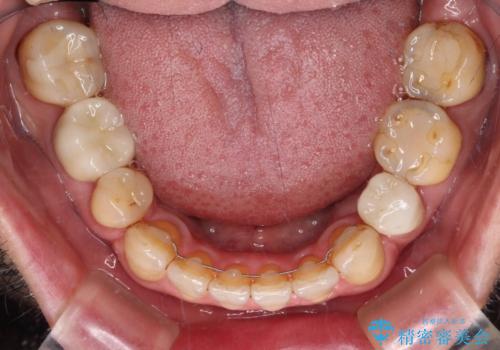

痛みは速やかに引き、銀歯や黒く変色したむし歯がセラミッククラウンで自然な色合いに仕上がり、患者様には大変満足していただきました。